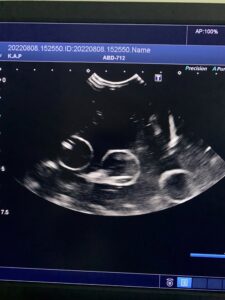

ですがちゃんと理解していないと、検査画像を見ても何がなんだかさっぱりわかりません!今日は少々マニアックですが、エコー検査の見方をご紹介します。

基本的にエコー検査とは全て「断面」で見ています。同じものでも、見る方向(断面)によっては全く違う様子で見えますよね。

下の写真に写っているエコー検査画像は、水の中に浮かんだ「あるもの」を2つの断面で見たものです。さて、「あるもの」とはなんでしょう?

※臓器ではありません。身近にある日用品(?)です。